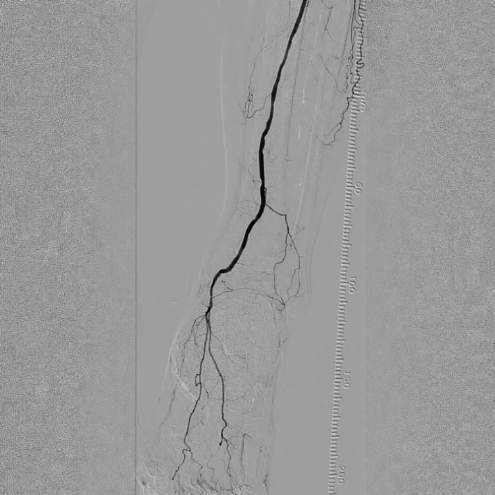

造影显示:胫腓干动脉血流恢复通畅,支架形态及位置理想,胫后动脉显影较术前明显改善;

腔内超声证实:铁支架完全张开、贴壁良好,无明显残余狭窄。